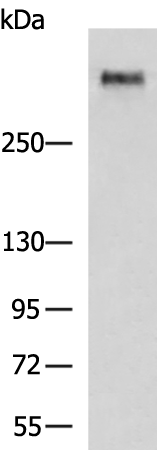

分类: 科研抗体货号: P11267别名: MG1; MUC5; MUC9; MUC-5B应用: WB,IHC反应种属: Human